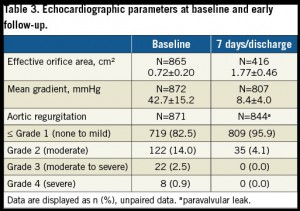

留置後の圧較差は8.4 mmHgであった。

Grade 2以上のPVLはSmall 4.4% (n=10), Medium 3.3% (n=12), Large 5.1% (n=13)で認められた。

また、”supra-annular” デザインであることより有効弁口面積が大きく取れ、術後の平均圧較差が小さくなっている。術後のARに関しても中等度以上は4.1%と、他の弁;Evolut R (8.5%), Direct Flow (3%), SAPIEN 3 (3.1%), Portico (3.8%-5.7%)とほぼ同様である。